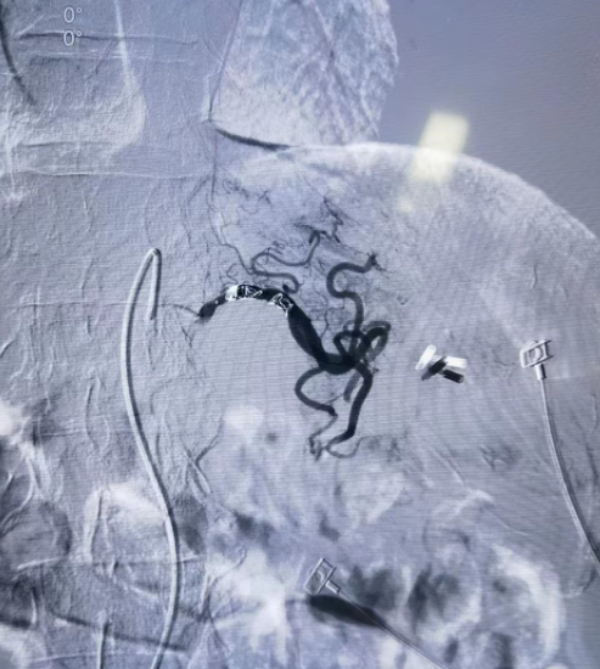

请血管外科宋海龙主任医师会诊后,决定立即行介入栓塞治疗。术中可见粗大的病变血管显影,给予弹簧圈及明胶海绵等栓塞剂后病变血管远端血流消失,止血效果立竿见影。